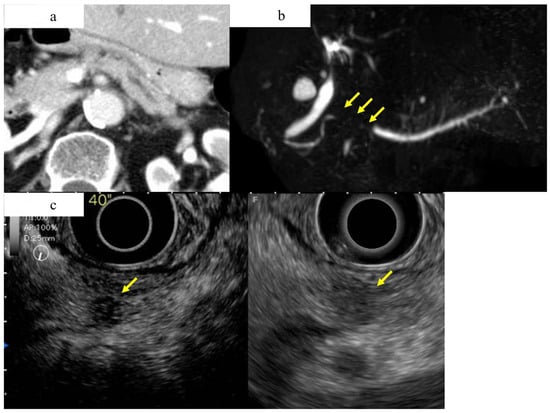

Figure 6.

A case of small ductal carcinoma of the pancreatic tail, imaged as a hard mass by EUS elastography (a), and a case of autoimmune pancreatitis of the pancreatic tail, imaged as a soft mass by EUS elastography. (a) Fundamental B-mode of EUS showing a 13 mm well-defined hypoechoic mass with irregular contours in the tail of the pancreas (yellow arrow). This tumor was shown to be a hard tumor on EUS-EG and was diagnosed as PDAC surgically. (b) Fundamental B-mode of EUS showing a 15 mm hypoechoic mass with an indistinct border and irregular outline in the tail of the pancreas (yellow arrow). This tumor was shown to be a relatively soft tumor on EUS-EG and was diagnosed as autoimmune pancreatitis by EUS-FNA.